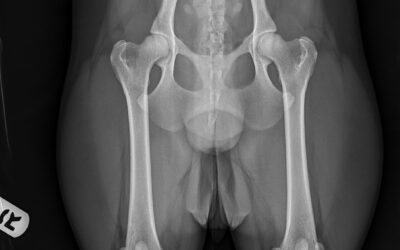

hip dysplasia screening

Learn here are some reasons why it is so important to screen your dog for Hip Dysplasia